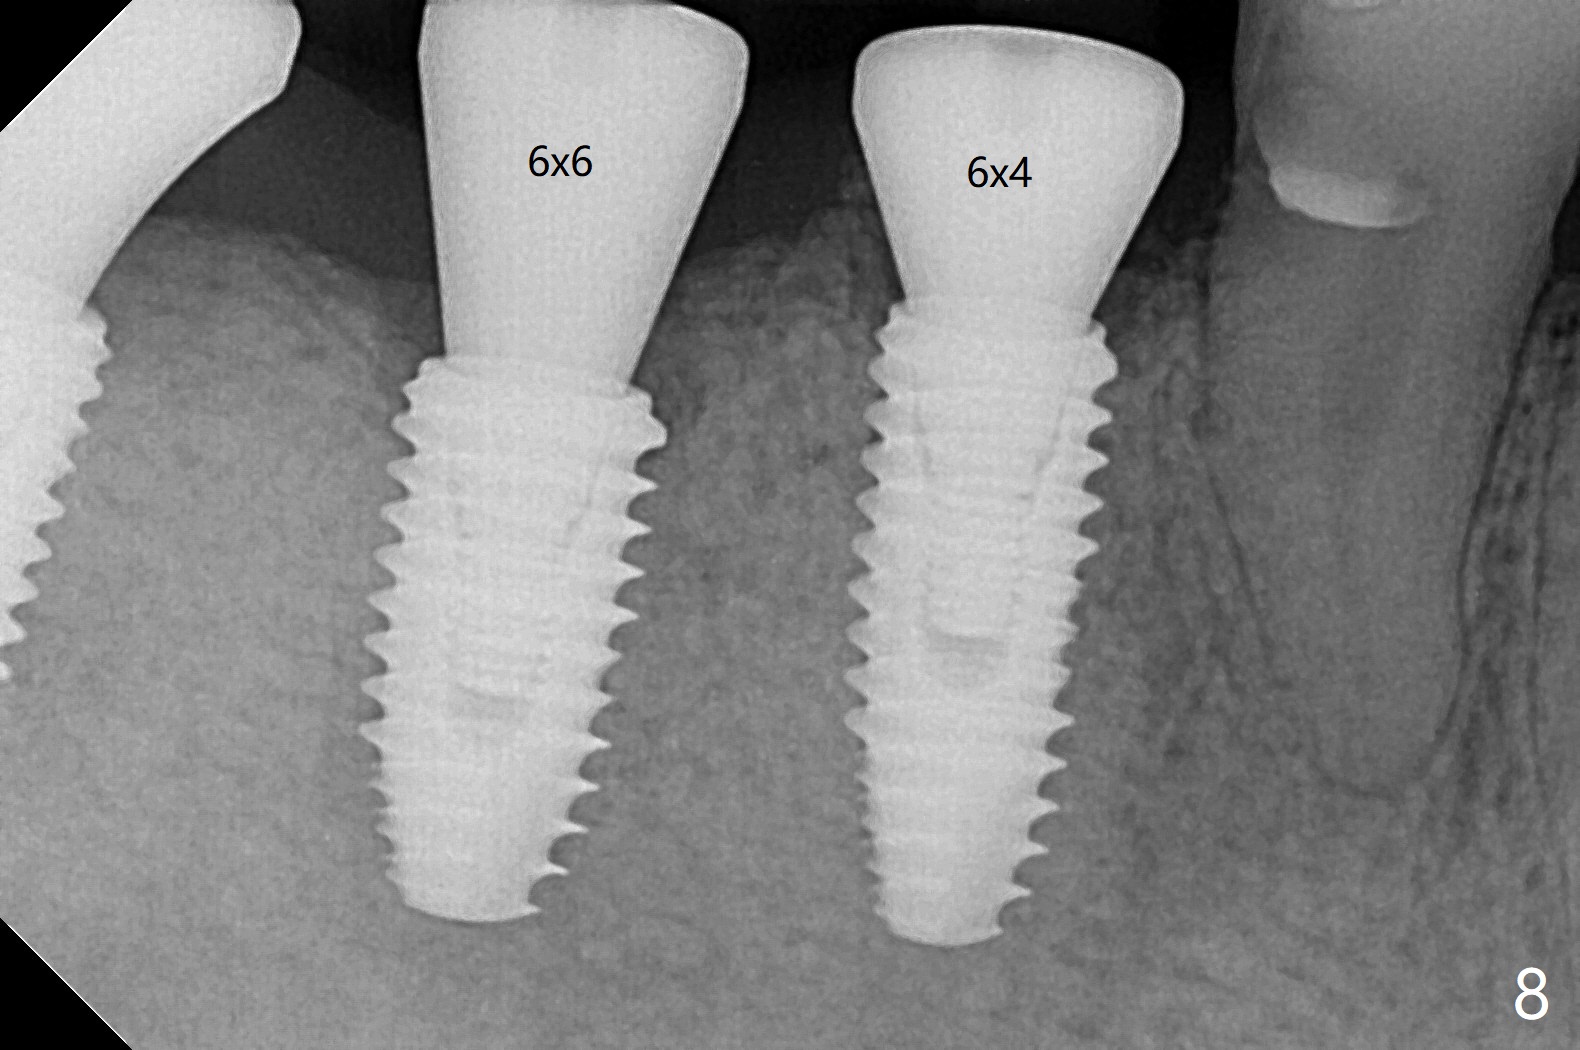

Five months post #31 implant removal with bone graft, osteotomy is initiated for a 5x10 mm implant using an existing guide. A question arises suddenly whether the bone height is reduced. Therefore a 4.5x10 mm dummy implant is placed with a fixture anchor placed at #30 (Fig.1 A). After using 4.5x8.5 mm drill with regular offset, a 5x10 mm definitive implant is placed with ~ 35 Ncm (Fig.2,3). After placement of the implant .5 mm deeper, a 8x6 mm healing abutment is placed, while the abutments return to #29 and 30 for splinted provisional (Fig.4). Two months later, the cemented abutment at #29 is loose (Fig.5) and retightened, but it remains incompletely seated for another 3 months (Fig.6). So is the one at #31 (Fig.6). After use of 4.6 and 5.6 mm bone profile drills, healing abutments are placed with apparently complete seating (Fig.7,8).